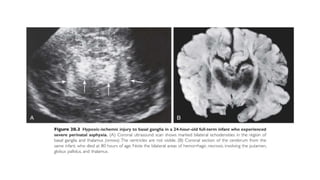

CRANIAL ULTRASONOGRAPHY

• Most commonly used neuroimaging modality in NICU

• Only modality available if the neonate is unfit for transfer

• Sensitive for parenchymal hemorrhage, ventricular size, gross brain

malformations, cystic changes in the brain, deep nuclear gray matter injury

• Resistivity index (normal: 0.65-0.90), less than 0.5 and more than 0.9 abnormal

• The changes are usually not detectable in 1st 24-48 hours